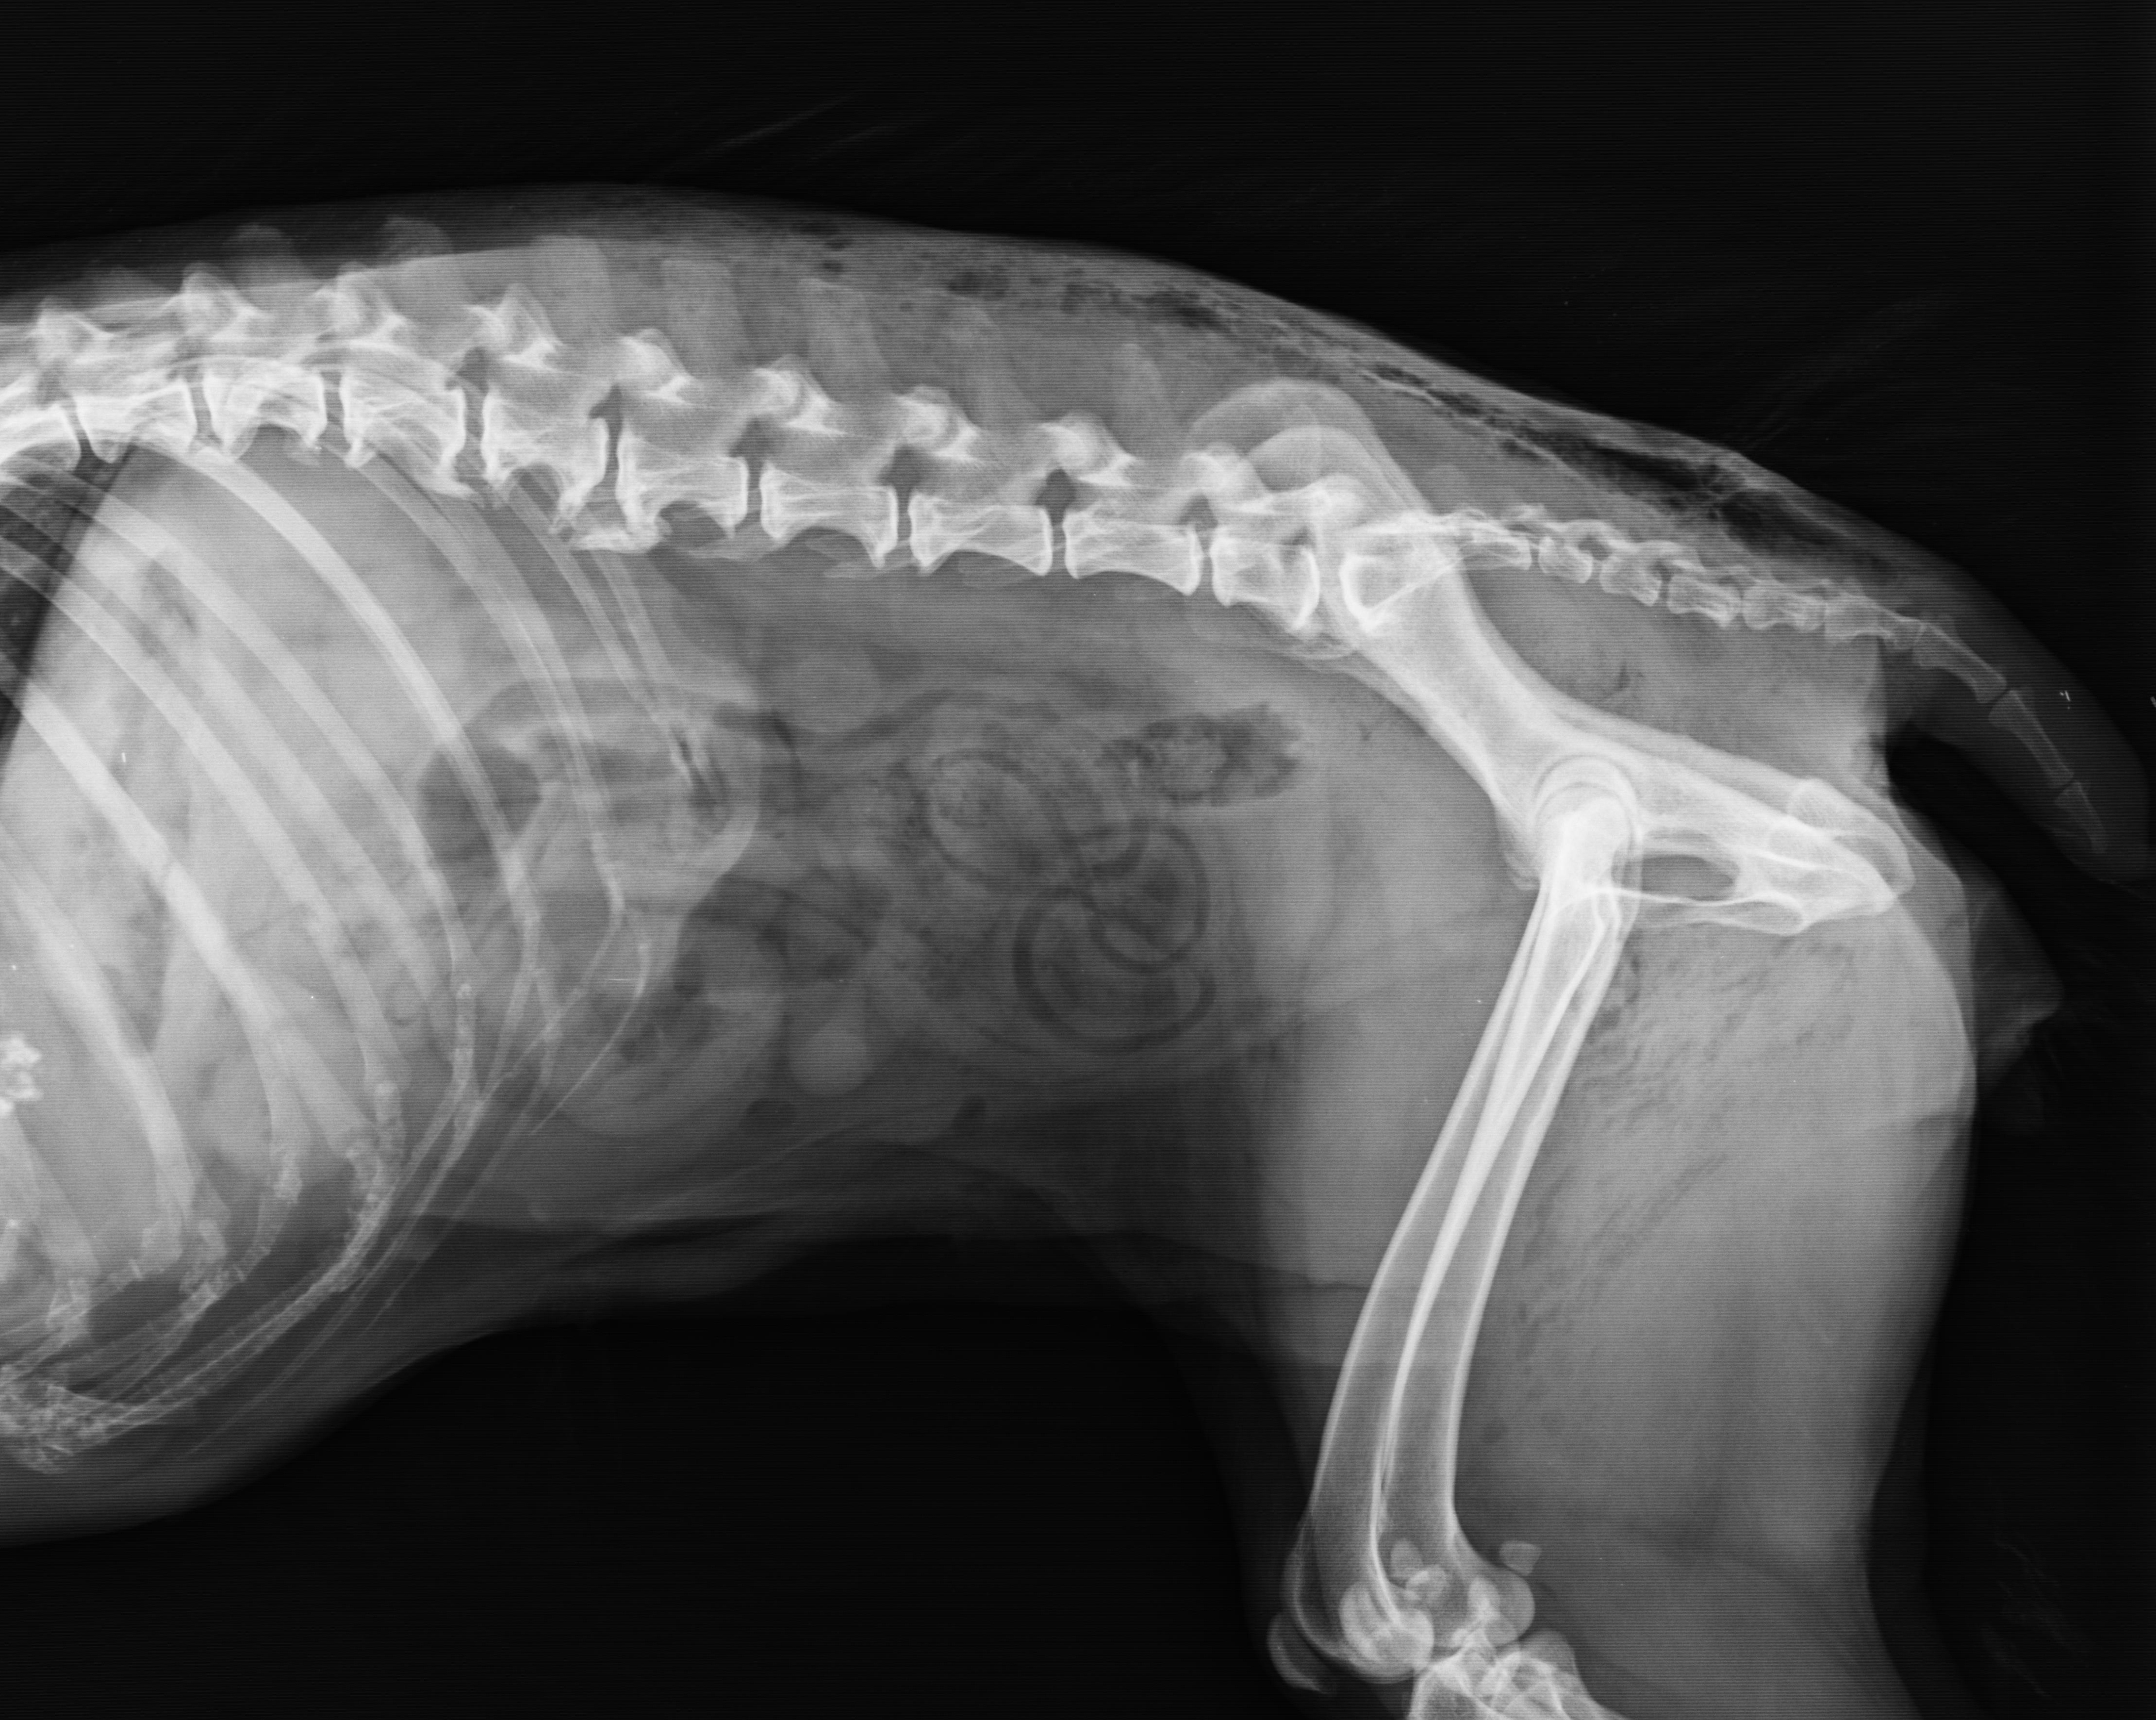

Spinal Arthritis